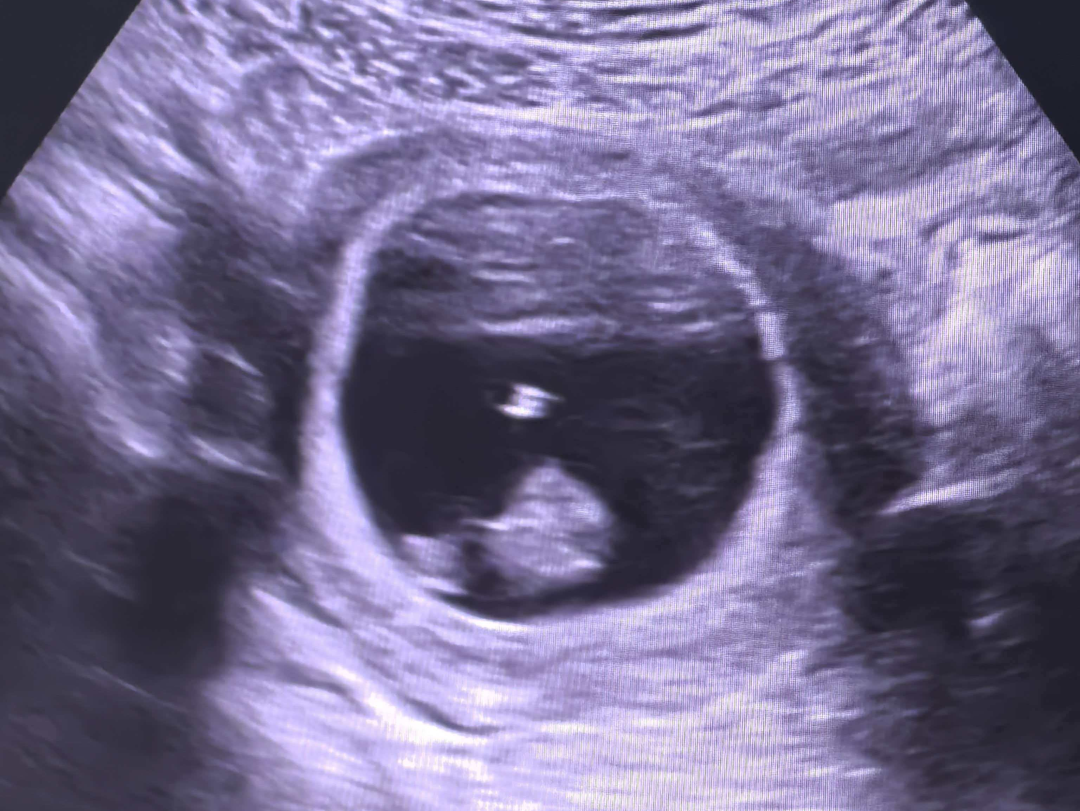

通过血HCG、孕酮检测及B超检查,准确确认怀孕,判断孕周,查看胎心胎芽,评估早期胚胎发育情况。

停经约6–8周

此时通过B超通常可见胎心胎芽,是早孕期一次关键检查。